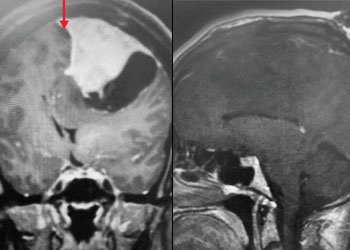

A) Pre-operative, post-contrast, coronal MRI. Arrow points to tumor involvement in the superior sagittal sinus

Fig 1. A) Pre-operative, post-contrast, coronal MRI. Arrow points to tumor involvement in the superior sagittal sinus.

B) Post-operative, post-contrast, coronal MRI

Fig 2. B) Post-operative, post-contrast, coronal MRI.

Treatment: Given the size and location of this tumor, the best treatment was surgical removal. Surgery was performed by Dr. Michael Brisman. A craniotomy exposed the tumor along the convexity as well as the superior sagittal sinus. The tumor was removed, as was the involved convexity dura and the affected segment of the sagittal sinus. Removed dura and skull were replaced with duraplasty (with artificial dura) and a titanium mesh cranioplasty.

Outcome: The patient did very well and made a full recovery.